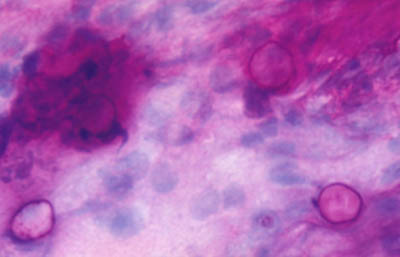

A - CW B - Giemsa C - PAS D - Gram

Tinción Giemsa

Magnificación 160x

Magnificación 160x